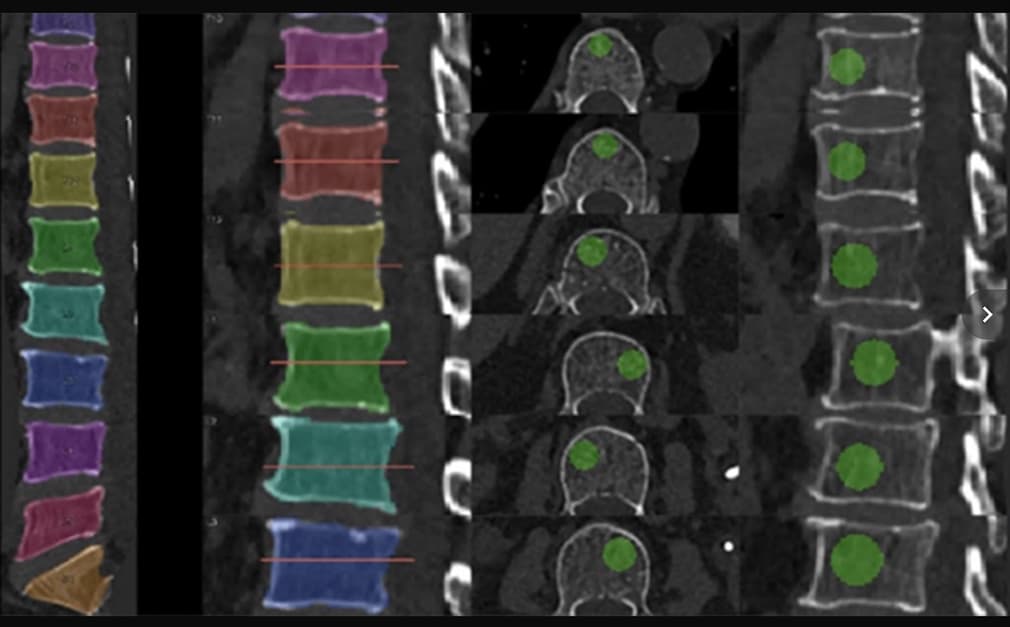

Dépistage opportuniste de fracture par TDM quantitative dans le cadre d'une déminéralisation osseuse

La tomodensitométrie quantitative serait une bonne alternative à l’ostéodensitométrie pour le dépistage de la fracture par déminéralisation osseuse. Pour gagner en précision dans l’évaluation de la DMO par TDM, une étude introduit le deep learning afin de définir une norme d’atténuation trabéculaire...

Un nouvel algorithme de détection des fractures vertébrales obtient le marquage CE

La société française Avicenna.AI a annoncé, le 5 juin 2025, l'obtention du marquage CE pour CINA-VCF Quantix, son nouvel algorithme d'IA conçu pour détecter et évaluer les fractures vertébrales par compression (FVC) non détectées à la tomodensitométrie (TDM).